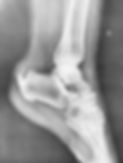

Arthroscopie antérieure de cheville : Lésions cartilagineuses et conflits

La cheville peut présenter des lésions cartilagineuses suite à des traumatismes ou microtraumatismes répétés lors d’activités sportives.

Il s'agit de lésions cartilagineuses du dôme astragalien de la cheville formant ainsi des Lésions Ostéochondrales du Dôme Astragalien (LODA). Il peut également y avoir des calcifications sources de douleurs (conflit de cheville).

Quand la lésion est de faible surface (ce qui représente la grande majorité des cas), le traitement proposé est une arthroscopie antérieure de cheville.

Grâce à 2 incisions (caméra et instruments), on peut explorer la moitié antérieure de la cheville : les corps étrangers sont retirés (excision-curetage), et l’os est perforé (microperforations) pour permettre une cicatrisation du cartilage par un tissu de substitution (fibro-cartilage).

Les éventuels conflits sont fraisés. Cette intervention permet une guérison dans 85% des cas. L’intervention se pratique en hôpital de jour.